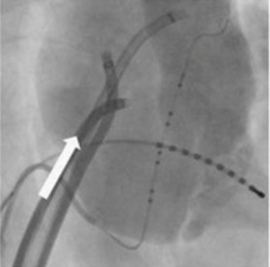

首や鎖骨の下、足の付け根などから細いカテーテルといわれる治療用の器具を心臓に挿入します(下図)。静脈を通して電極カテーテルという直径2mm程度の細いチューブを3から5本心臓の中に進め、肺静脈、洞結節付近、房室結節付近、右心室、冠静脈洞内部などに不整脈の回路を同定するために配置します。